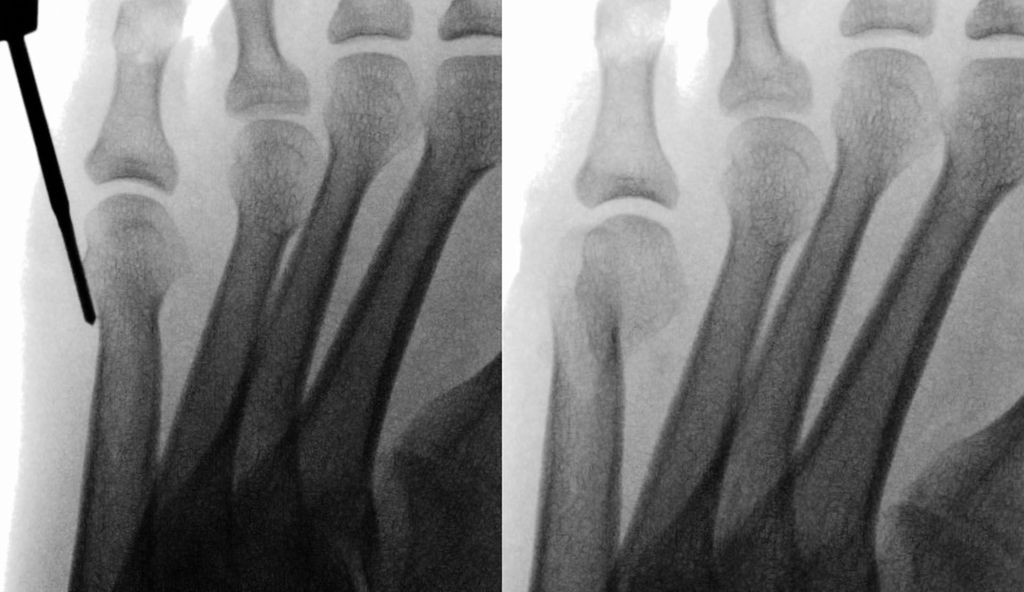

Isolierte Überlängen von Zehen können mit minimalinvasiven Osteotomien an der Grundphalanx sehr gut korrigiert werden (Abb. 6). Bei Fehlstellungen in der Transversalebene wird ebenfalls über eine Stichinzision in Höhe der Fehlstellung eine Kortikotomie durchgeführt und die Fehlstellung durch Schließen der Osteotomie korrigiert (Abb. 7).

Die Nachbehandlung erfolgt mit Tape-Zügeln im postoperativen Schuh.